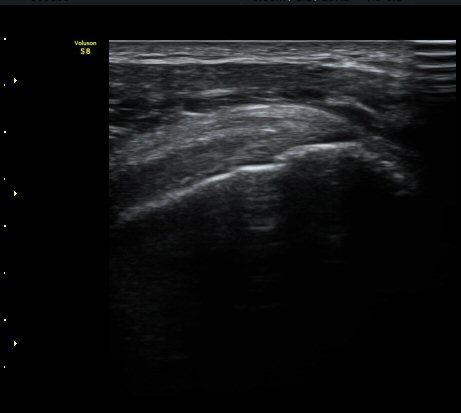

±Ø»ó°Ç Á¾´Ü¸é°Ë»ç¿¡¼­ ´ë°áÀý°ú »ó¿Ï°ñµÎ ÀÌÇàºÎÀ§¿¡ ÇÇÁú°ñ ¿¬¼Ó¼º ¼Ò½ÇÀ» º¸ÀÓ(±×¸² 3, 4, 5)